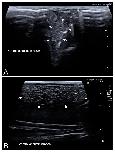

Figure 4. Representative high-resolution ultrasound (HR-US) images of a female Kaloula pulchra obtained in the transverse plane (A) and a female Xenopus laevis (B) obtained in the longitudinal plane using, in both cases, a ventral acoustic window. Follicles appeared as a complex of anechoic or hypoechoic rounded or oval areas separated by hyperechoic lines. |

Figure 5. HR-US images of a female Xenopus laevis in the longitudinal plane using ventral (A) and dorsal (B) acoustic windows. Although the complex of follicles is clearly identified in both, the ventral acoustic window was considered more adequate for the examination of female gonads. Nevertheless, the kidney (k) was better identified using the dorsal acoustic window. |